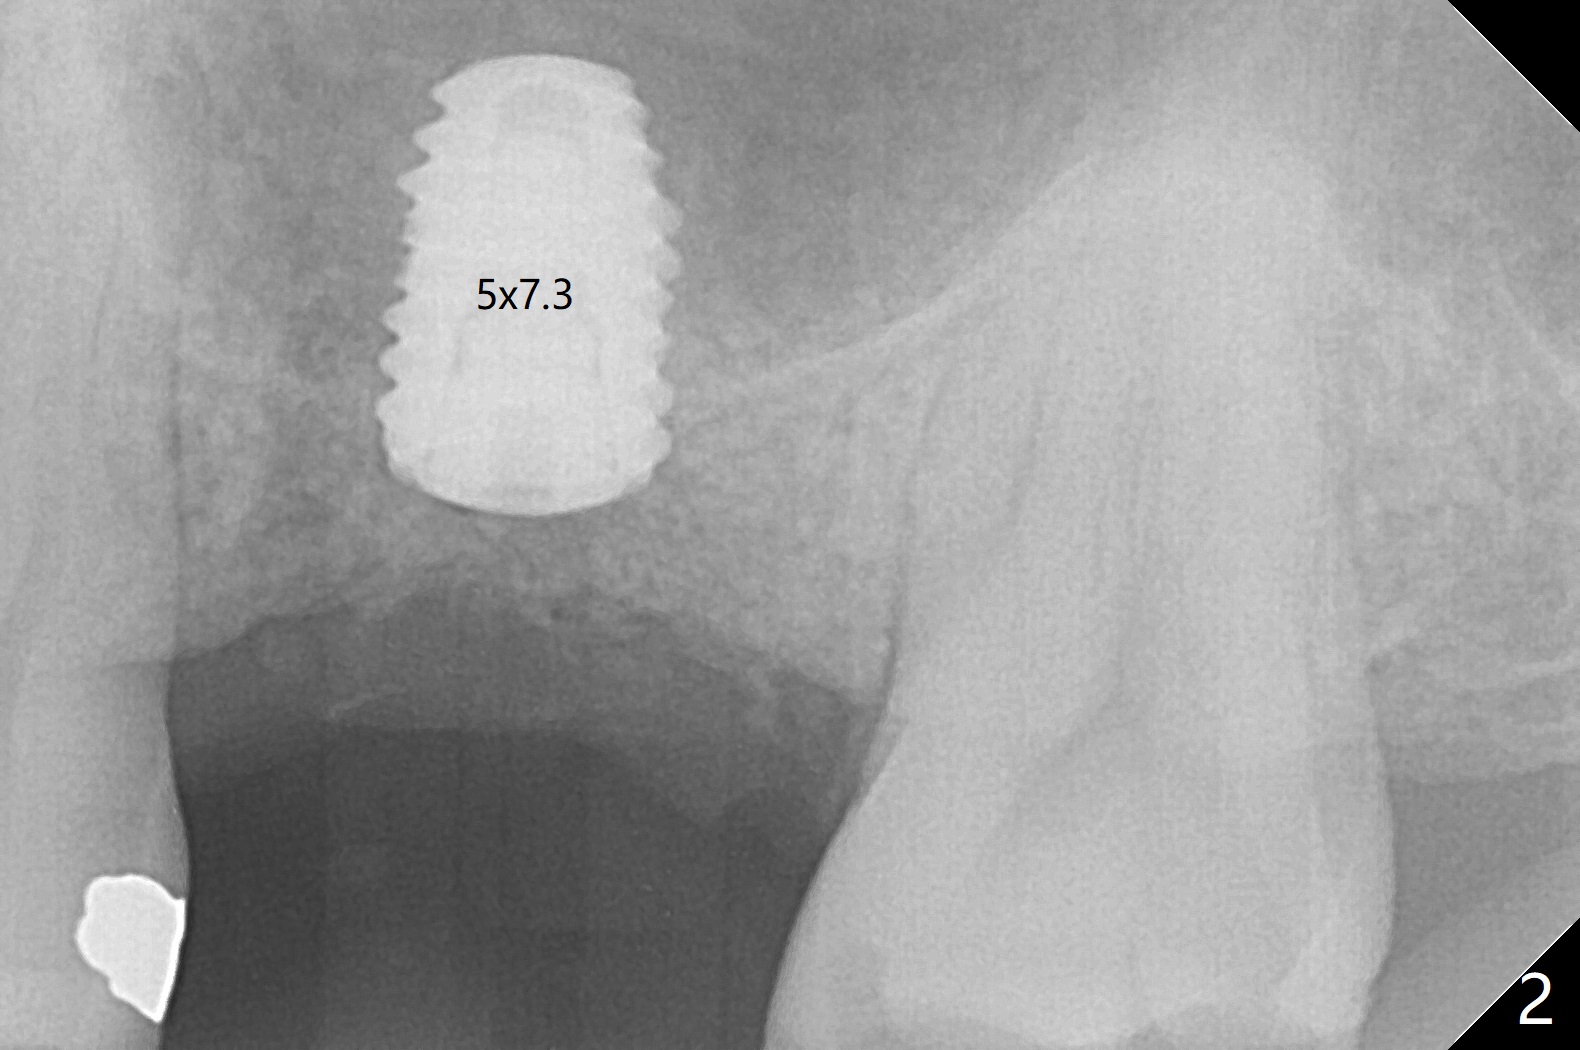

After using 4.5x5.3 mm and 3.5x7.3 mm drill at #14 with guide, the sinus floor is not perforated. When a 4.5x11 mm dummy implant is placed to the 2nd line (12 mm offset), the sinus membrane is perforated (Fig.1). A piece of PRF membrane and sticky bone are pushed into the sinus in an attempt for repair. A shorter implant is placed (5x7.3 (instead of 8.5) mm, Fig.2,3,5, as compared to Fig.3) to reduce postop sinus infection. In fact incision reveals palatal bony concavity. When the implant is placed, there is mild palatal thread exposure. With incision instead of tissue punch, it is easy to place bone graft over the small defect (Fig.3 *). The wound dehisces and heals 2 weeks postop (Fig.6). There is bone loss 6.5 months postop (Fig.7 *), corresponding to palatal thread exposure. After decortication and periosteal underscoring, cortical allograft mixed with ~.25 cc GEM21S is placed (Fig.8 *).